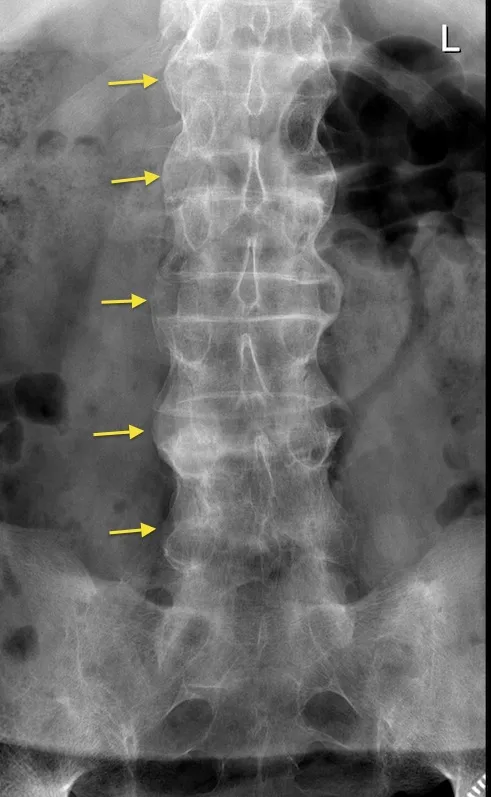

- Classic "Bamboo Spine" appearance on X-ray (late finding due to syndesmophytes & vertebral fusion).

- Ankylosing Spondylitis: progressive spinal fusion ("bamboo spine"), morning stiffness.